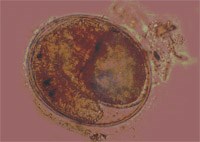

- Để xác định đúng nguyên nhân gây bệnh sán lá gan nhỏ do cá giếc, chúng tôi đã dùng ấu trùng sán lá gan nhỏ thu hồi ở cá giếc sống (Metacercaria) đem gây nhiễm cho mèo non tại labo của Viện sốt rét KST - CT Quy Nhơn. Qua 4 tháng gây nhiễm cho 3 con mèo non và có 2 mèo non đối chứng, khi mổ gan mèo gây nhiễm đã thu hồi 314 con sán lá gan nhỏ từ non đến già. Riêng 2 mèo đối chứng chỉ cho ăn cơm và cá chín, khi mổ không tìm thấy sán trong gan mèo.

- Tại điểm nghiên cứu chúng tôi thu thập một số mèo địa phương để mổ gan tìm sán. Kết quả mổ 10 con mèo có tuổi đời từ 1- 6 năm thu được 404 con sán lá gan nhỏ.

Hình ảnh con sán lá gan nhỏ được tìm thấy ở mèo tại An Mỹ |

- Sau khi thu hồi sán lá gan nhỏ ở các vật chủ mèo nuôi, mèo gây nhiễm và ở người, chúng tôi đã xử lý và ép nhuộm làm tiêu bản định loại. Kết quả định loại theo các tiêu chuẩn hình thái học cho thấy tất cả sán lá gan thu hồi ở các vật chủ trên đều là loài sán lá gan nhỏ Opisthor chis viverrini.

Kết quả định loại hình thể học của chúng tôi đã được GS-TSKH Nguyễn Thị Lê, Viện Khoa học Việt Nam kiểm chứng đúng tên loài và được báo cáo nghiệm thu tại Hội đồng chấm luận án Tiến sỹ Y học cấp Nhà nước năm 2000. Loài sán này tiếp tục được kiểm chứng bằng kỹ thuật PCR của Viện Khoa học Việt Nam năm 2003 đều thống nhất kết quả là loài sán lá gan nhỏ Opisthor chis viverini.